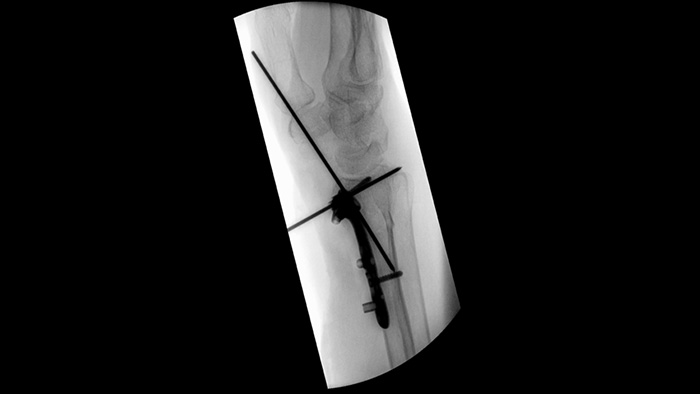

Vereenvoudig de workflow voor complexe orthopedische procedures waarbij de mobiele C-boog regelmatig opnieuw moet worden gepositioneerd. Uit een bruikbaarheidsonderzoek1 bleek dat er met Position Memory2 in 94% van de gevallen direct de juiste herpositionering werd gerealiseerd en dat er minder frustratie werd ervaren tijdens (her)positioneringstaken.

Unieke asymmetrische sluiters vergroten de flexibiliteit van de collimatie en helpen u de anatomie te collimeren met behulp van sluiters die u afzonderlijk kunt plaatsen met uw vingers. U kunt de sluiters en de beeldoriëntatie aanpassen terwijl het laatste beeld wordt vastgehouden zonder straling te gebruiken.